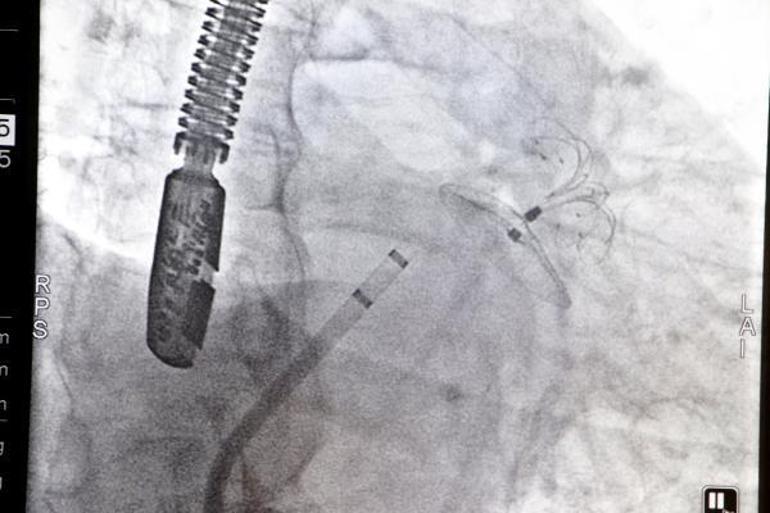

İnce'ye, 'sol atriyal apendiks kapama' (kalbin sol kulakçığındaki kör boşluğun kapatılması) operasyonu yapıldı. Prof. Dr. Teoman Kılıç başkanlığında Prof. Dr. Mesut Demir, Doç. Dr. Çağlar Özmen, Doç. Dr. Emre Çağlıyan ve Yrd. Doç. Dr. Rabia Akıllı'dan oluşan ekibin yaptığı operasyon başarıyla sonuçlandı. Bir süre yoğun bakımda izlenen İnce, daha sonra servise alındı.

Bazı hastalarda tekrarlayan kanamalar nedeniyle bu ilaçlar kullanılamamakta ya da bu ilaca rağmen inme gelişebilmektedir. Böyle durumlarda kalp kökenli pıhtıların en önemli kaynağı olan sol kulakçıktaki kör boşluğun ağzına tıpa konulup, yeni oluşan pıhtıların beyne gitmesini önlenmektedir. Böylece hasta hem ilaç olmaksızın inme riskine karşı korunmakta hem de ilaca bağlı kanama olasılığı ortadan kalkmaktadır" dedi.

"Bu bölgeyi özel olarak geliştirilmiş yeni, teknolojik bir cihaz ile kapatarak, kalpten beyine pıhtı atmasını engellemiş oluyoruz. Bu durum genelde erişkinlerde olan 'atriyal fibrilasyon' dediğimiz ritim bozukluğundan kaynaklanıyor. Ritim bozukluğunda en çok korktuğumuz durum; beyine pıhtı atması ve felçlik durumudur.